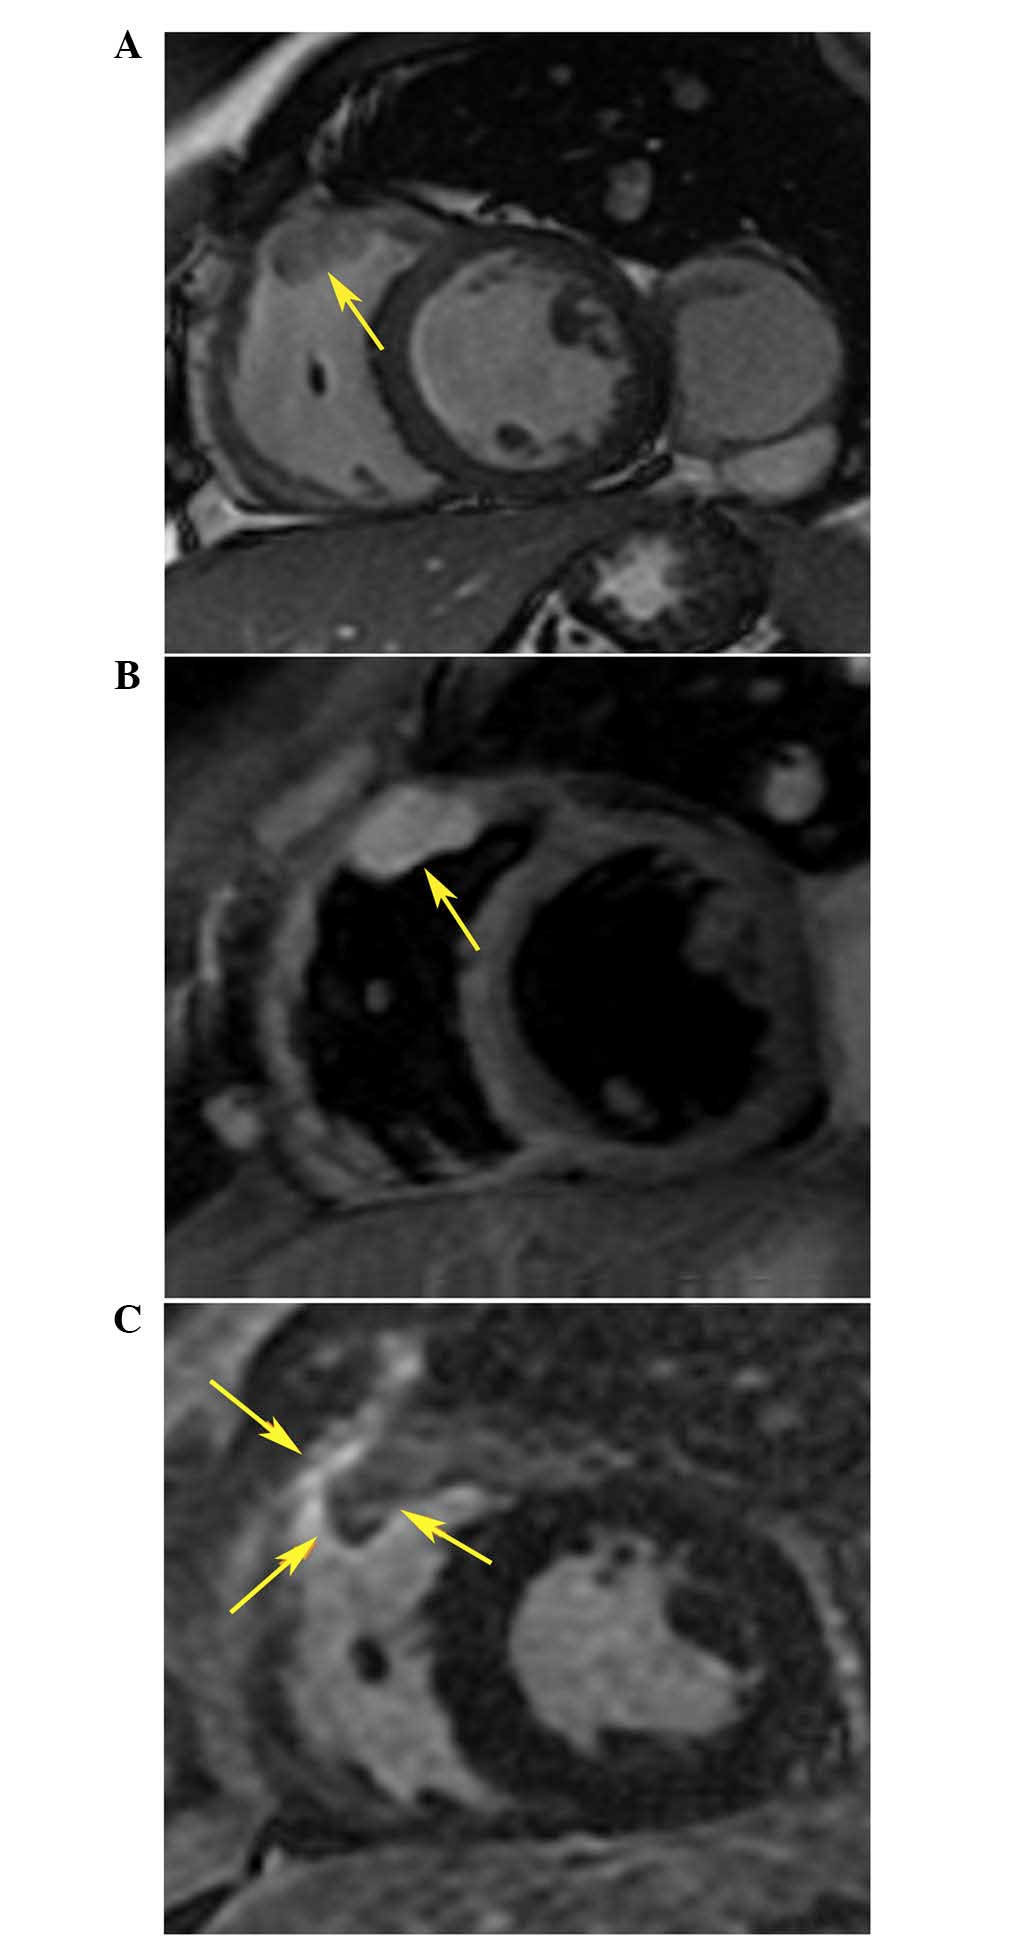

Figure 4.

(A) T1-weighted (low signal intensity) cardiac magnetic resonance imaging of the mass (indicated by arrows) in the right ventricular outflow tract. (B) High signal intensity in T2-weighted imaging. (C) High signal intensity post-ablation cardiac magnetic resonance shows the ablation line (indicated by arrows) surrounding the mass.

Following the procedure, the patient no longer complained of palpitations or dyspnea. Ambulatory Holter monitoring revealed one episode of accelerated ventricular rhythm similar to RVOT VT 2 days after ablation. In addition, a CMR scan showed the presence of an enhanced area surrounding the metastatic tumor within the RVOT (Fig. 4C), which was compatible with ablation points. AADs were discontinued 1 month after ablation, and no ventricular arrhythmia was recorded by Holter monitoring in the 8 months follow-up.

The general condition and past history of patients should be carefully monitored if typical RVOT-VT could not be ablated or recurs following several procedures. In these cases the RVOT may be affected by malignant metastatic tumors and may become an arrhythmogenic foci. CMR is particularly useful for identifying cardiac metastases due to its ability to provide tissue characterization (19,20); the mass-infiltrated RVOT of the patient emitted a low signal intensity on the T1-weighted CMR image and a high signal intensity on the T2-weighted CMR image, which was compatible with the CMR characteristics of malignant tumors and ESMCs (19,20).